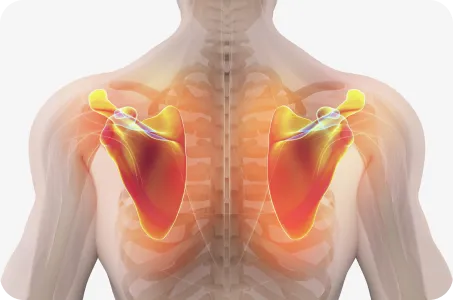

굽은 등의 경우, 견갑골의 위치가 척추에서 멀어져 있으며, 어깨 앞쪽의 근육은 긴장되어 있고 뒤쪽 근육은 늘어나 있습니다. 이 상태로 팔을 사용하게 되면 어깨의 건(힘줄)과 주변 인대가 늘어나거나 끊어지기 때문에 아픈 부위만 계속 치료한다면, 통증은 재발할 수 밖에 없습니다.

장기 치료 전략견갑골의 위치를 바로잡아, 어깨가 움직일 때 과도하게 사용되는 근육이 없도록 하는 원인 치료

굽은 등과 편평등은 견갑골의 위치를 틀어지게 만드는 주범으로 등뼈가 정상적인 커브를 이루고 있을 때 어깨가 가장 편하고 바른 자세가 됨